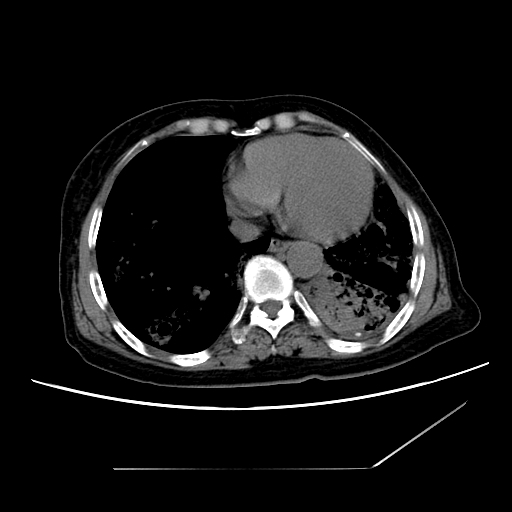

标题: CT25393:病人45岁,咳嗽,吐黄痰带血丝,发热,胸闷月余

1、左肺中央型肺癌并双肺弥漫性转移   2、双肺部感染    3、肺大泡     4、左侧胸腔积液

双侧肺弥漫性病变,可见“空泡征”及“蜂窝征”,考虑肺泡癌可能性大,左侧胸腔积液,考虑胸膜受累可能!

1)不排除肺泡癌可能。2)左侧胸腔积液。